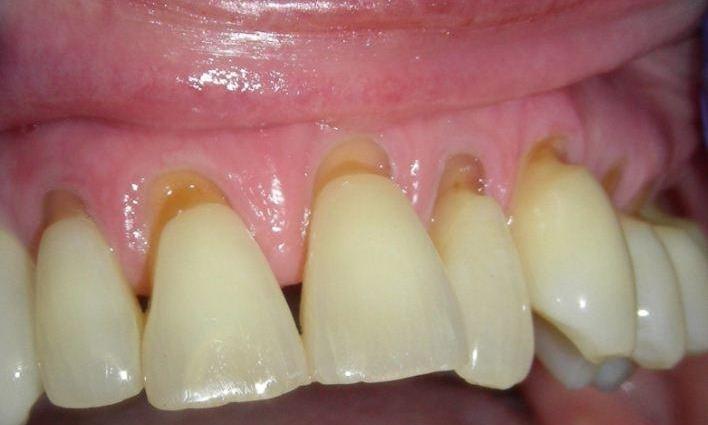

Laminate composite resin veneers

This patient came to our office with severely eroded enamel. This condition can result from excessive use of acidic foods (such as lemons or soda), or other causes.

When the enamel is not present to protect the teeth, the softer dentin underneath is far more vulnerable to further destruction.

This case was restored with composite resin veneers, and was completed in one session. In cases such as this, little or no drilling of the natural tooth structure is necessary.